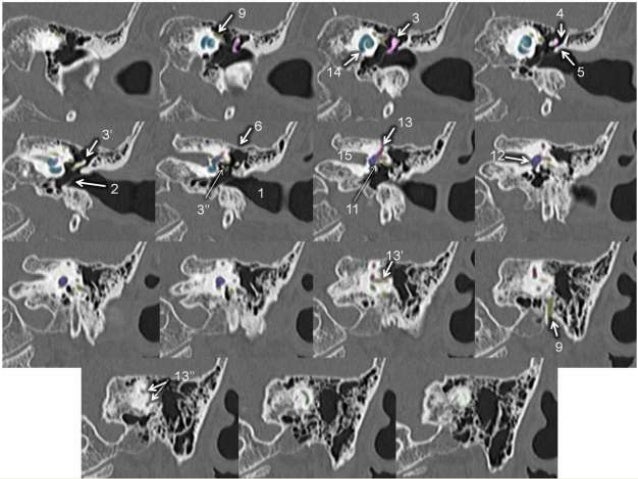

Facial Nerve Anatomy - Labeled CT | Image | Radiopaedia.org

Facial nerve anatomy - labeled CT | Image | Radiopaedia.org radiopaedia.org

nerve radiopaedia axial labeled